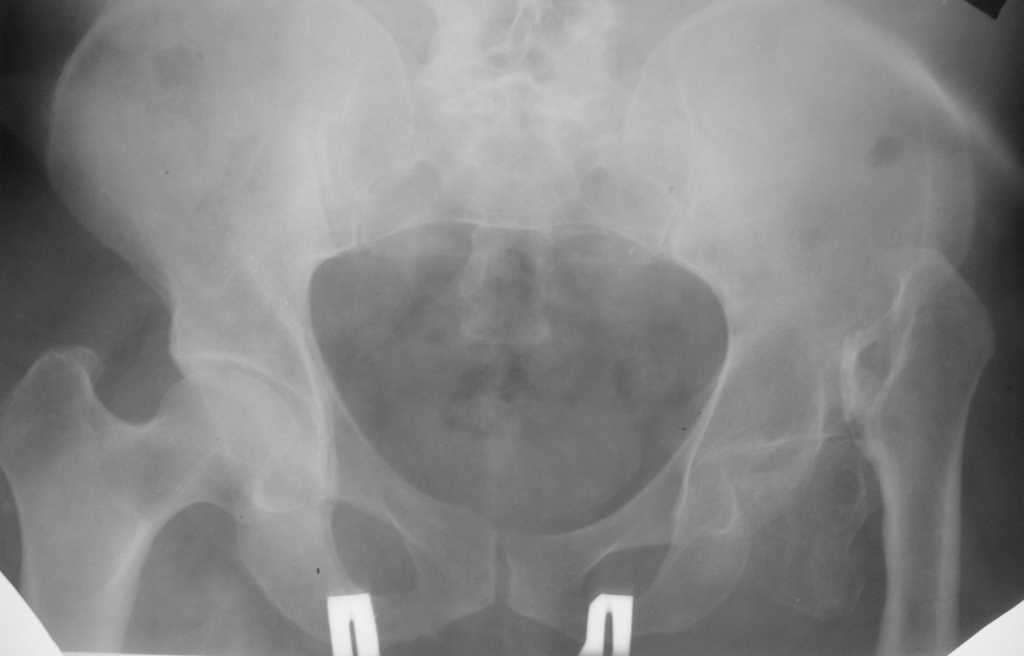

Приведу клинический пример несколько схожий с Вашим. Пациент 56 лет, 18 лет назад получил перелом шейки бедренной кости. Полноценного лечения не получил и остался с неопорным бедром. Укорочение было в районе 6-7 см. Первым этапом после миотомии приводящих мышц в теч. 2-х недель низвели бедро аппаратом Илизарова, далее сняв аппарат установили эндопротез гибридной фиксации (выраженный остепороз впадины ввиду отсутствия нагрузки). К сожалению, в процессе установки ножки эндопротеза произошёл перипротезный перелом медиальной стенки и профилактически мы наложили серкляжные швы. Контроль через 12 месяцев -укорочения нет, функция нормальная. Оперирован в 2005 году. с 2006 года к нам не обращался. АИФ